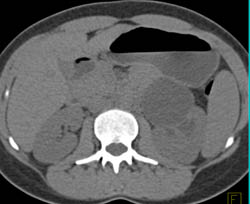

Diagnosis

Nice View of Pulmonary Valves in 3D